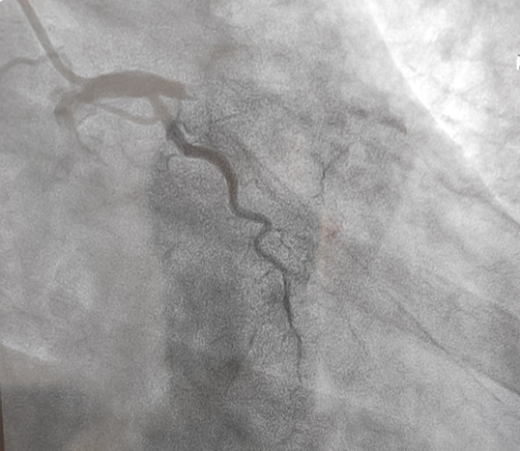

立即啟動綠色通道,急診冠脈造影,結(jié)果顯示前降支近段閉塞,血栓負(fù)荷較重,先后給予血栓抽吸及球囊擴(kuò)張,血流恢復(fù)正常。李桂武主任和劉興剛主任發(fā)現(xiàn)患者近段狹窄達(dá)70%,且中遠(yuǎn)段嚴(yán)重狹窄伴鈣化,此時不適合同期植入支架,如植入支架可能會引發(fā)血管破裂危及生命。當(dāng)務(wù)之急是快速評估出患者是否可以下手術(shù)臺,選擇擇期進(jìn)行處理,但僅根據(jù)造影結(jié)果又很難做出判斷,李桂武主任和劉興剛主任快速討論研究最后一致決定,給予患者行冠脈OCT檢查,明確病變性質(zhì)。

經(jīng)OCT檢查結(jié)果顯示:前降支中段鈣化,內(nèi)膜光滑,最小管腔面積僅為1.19 mm2。近段斑塊破裂,可見血栓影,最小面積為2.63mm2??蛇x擇先進(jìn)行抗栓治療,擇期處理冠脈病變。這讓張先生懸著的一顆心終于放下來。